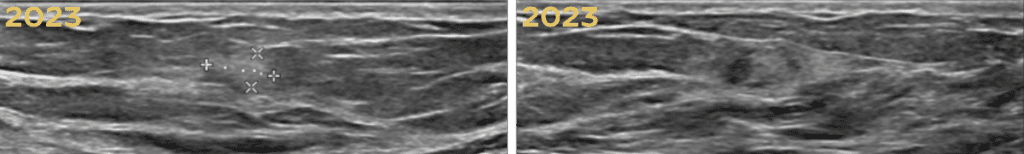

Hyperechogenicity is typically associated with benign breast lesions, including hamartoma, lipoma, angiolipoma, hemangioma, hematoma, fat necrosis, fibrosis, and galactocele. However, some rare malignant lesions may also appear hyperechoic.

Hyperechoic Breast Lesions

Biopsy-proven Invasive Lobular Carcinoma

Watch for subtle, suspicious features like irregular shape, non-circumscribed margins, non-parallel orientation, or posterior acoustic shadow.